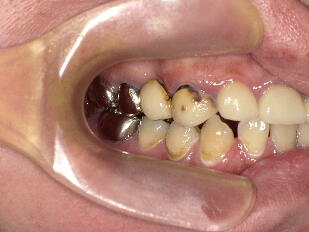

B、不適切な補綴治療によって低位咬合が生じ、審美的にも問題がありますが、耳鳴り、肩

こり等の身体的諸症状の誘発が懸念されました。 ![]() ![]()

上顎を左右理想平面にあわせた後、下顎の臼歯部を仮歯を用いて徐々に上げて理想状態

にし、しばらくの間身体的な諸症状が出現しないか確認した後、最終補綴物を装着しまし た。 4.部分矯正